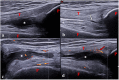

The interest and application of musculoskeletal ultrasound (MSUS) in juvenile idiopathic arthritis (JIA) are increasing. Numerous studies have shown that MSUS is more sensitive than clinical examination for detecting subclinical synovitis. MSUS is a well-accepted tool, easily accessible and non-irradiating. Therefore, it is a useful technique throughout JIA management. In the diagnostic work-up, MSUS allows for better characterizing the inflammatory involvement. It helps to define the disease extension, improving the classification of patients into JIA subtypes. Moreover, it is an essential tool for guiding intra-articular and peritendinous procedures. Finally, during the follow-up, in detecting subclinical disease activity, MSUS can be helpful in therapeutic decision-making. Because of several peculiarities related to the growing skeleton, the MSUS standards defined for adults do not apply to children. During the last decade, many teams have made large efforts to define normal and pathological US features in children in different age groups, which should be considered during the US examination. This review describes the specificities of MSUS in children, its applications in clinical practice, and its integration into the new JIA treat-to-target therapeutic approach.